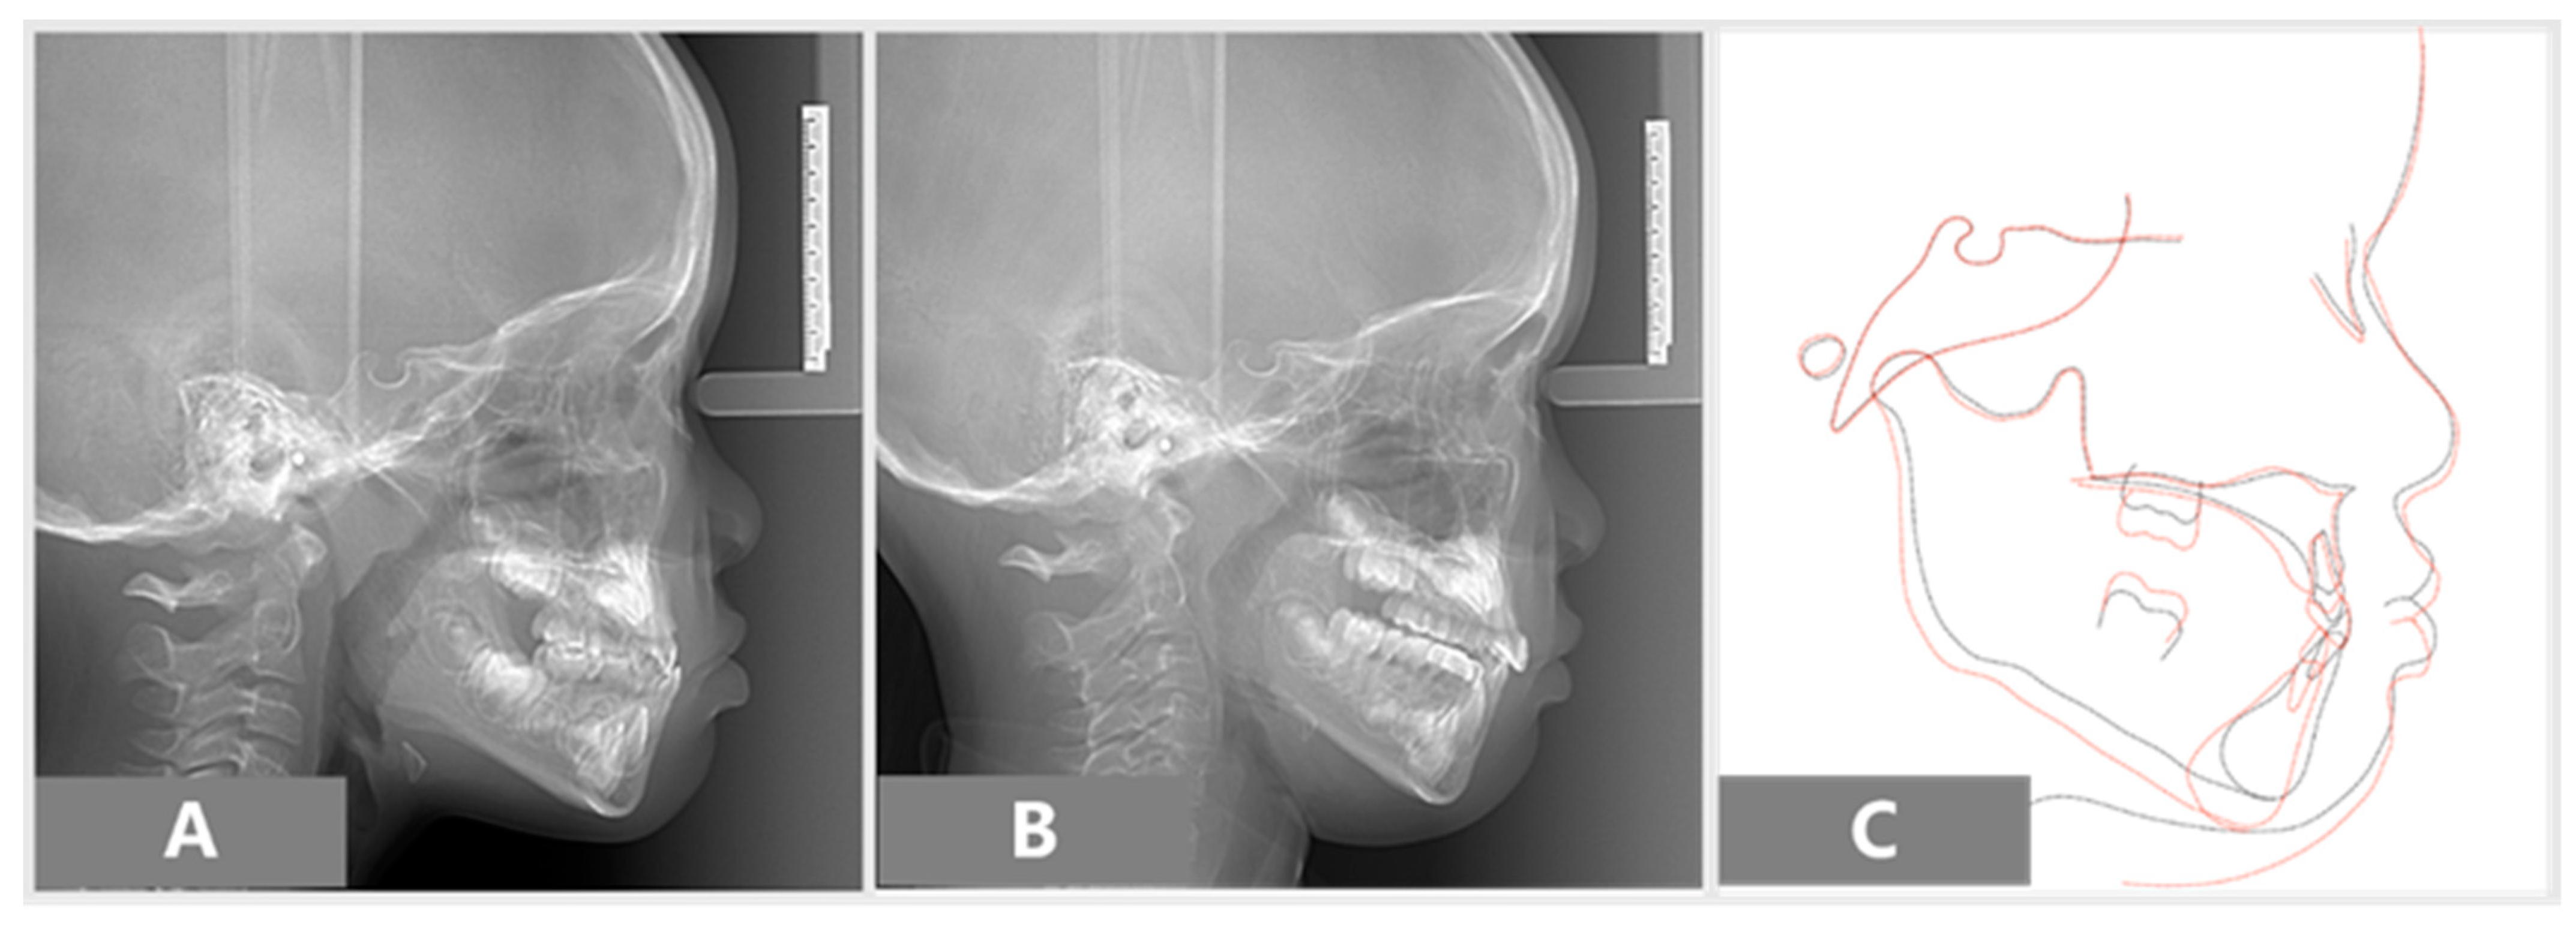

After 11 months of active treatment, the crossbite of the anterior teeth and the unilateral scissor bite on the right side were successfully corrected (Figure 3). The pre-treatment and post-treatment lateral cephalographs and panoramic radiographs are presented in Figure 4 and Figure 5. The pre-treatment and post-treatment lateral cephalometric data are presented in Table 1.

Figure 5.

Lateral cephalograms: (A) pre-treatment, (B) post-treatment, (C) superimpositions of pre-treatment (black line) and post-treatment (red line).

In the panoramic radiograph, she was in the primary dentition stage, all permanent teeth were present except for the third molars. The pre-treatment cephalometric analysis presented with mild Class III skeletal relationships (ANB 0 degree), a high negative value of Wits measurement (−4.5 mm), and the lower incisor inclination was 20 degrees to the NB. Linear measurements showed the maxilla was retrusive with the Nasion perpendicular to point A (−2.7 mm). She had the feature of a “strong chin” appearance—the lower lip was protruded relative to the upper lip.